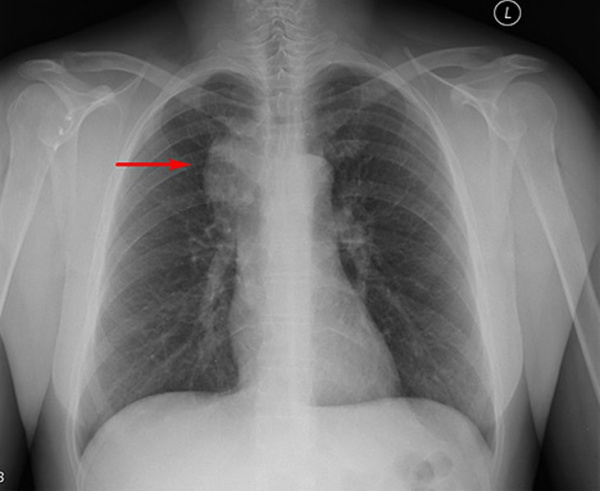

На поздних стадиях заболевания клинические проявления зависят от локализации гиперплазированной лимфатической ткани. Поражение узлов средостения сопровождается охриплостью голоса, затруднением дыхания и глотания, болями в грудной клетке. Разрастание внутрибрюшных лимфоузлов вызывает боли в животе, диспепсические расстройства, нарушения мочеиспускания.

При локальных формах основной проблемой остается нарушение функции соседних органов. Поражение внутрибрюшных узлов чревато развитием механической кишечной непроходимости, нарушением поступления желчи в 12-перстную кишку. При поражении средостения возможна дыхательная недостаточность. При этом показатели выживаемости намного лучше: 94,5% пациентов живут дольше 5 лет после постановки диагноза.